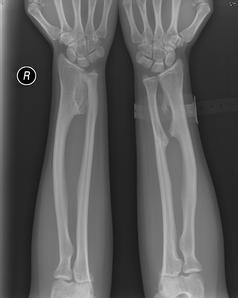

普通X线检查:长干上骨瘤的X线特点是表面上有一性突起,与干骺相连,并由皮质及松质所组成。常成对称性,多发性。由于肿基底部状不同,常可分成有蒂(有一窄部较宽)及无蒂(基底宽而扁)两种(图4)。骨瘤常发生在干骺端韧带附着处,其生长趋向与韧带所产生力的向一致。如软帽薄,边界清楚,带有规则点状钙化,这种表现为良性生长。如软帽大且厚,边界不清楚、带有不规则的钙化,则应注意其恶性变的可能。